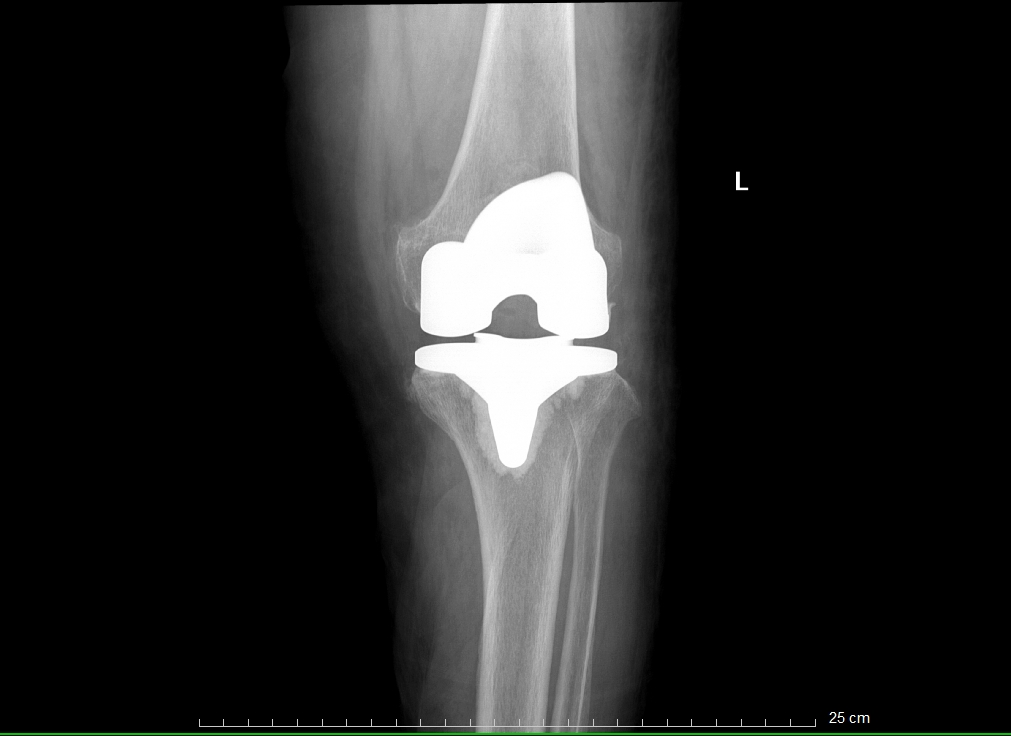

患者术后X光扫描

这个过程可以类比为镶牙,即切除受损部分并替换为金属材料。同理,在膝关节置换术中,医生会移除严重磨损的关节表面软骨及部分软骨下骨,在原位安装与原始膝关节表面形状类似的金属组件(即假体),使用骨水泥将假体与患者自身的股骨和胫骨固定在一起,使之恢复膝关节的正常功能。

患者术前VS术后对比